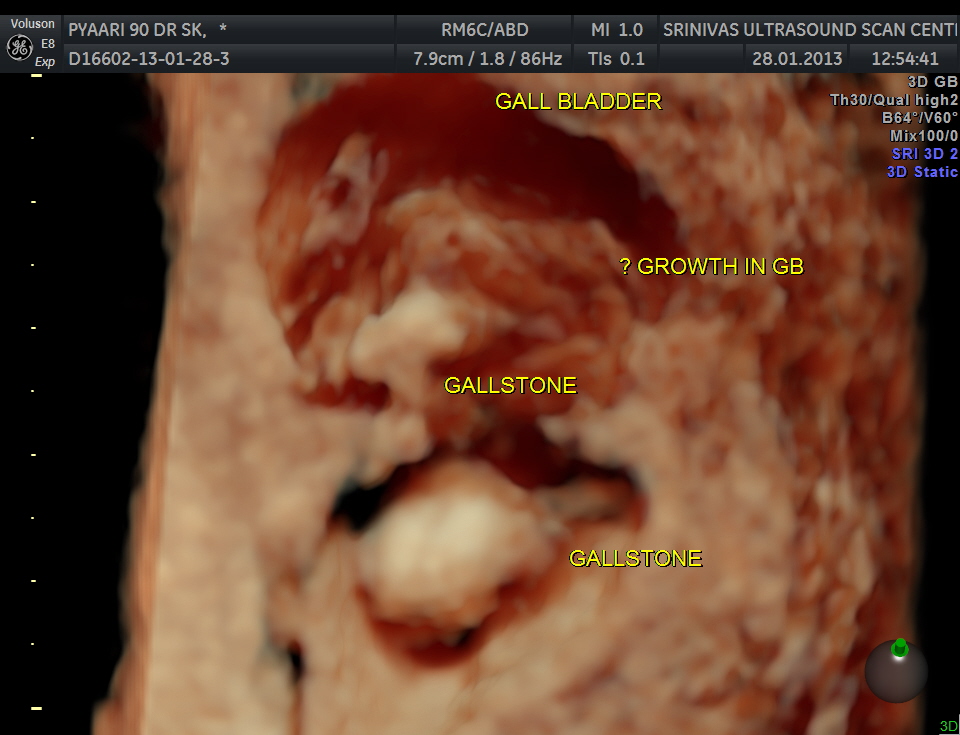

3 D view of the same.

The fundus shows irregular growth and a gallstone.

This 90 year old lady had many reasons for her symptoms. – CHOLELITHIASIS , PROBABLE GALL BLADDER WALL CARCINOMA AND MEDICAL RENAL DISEASE.